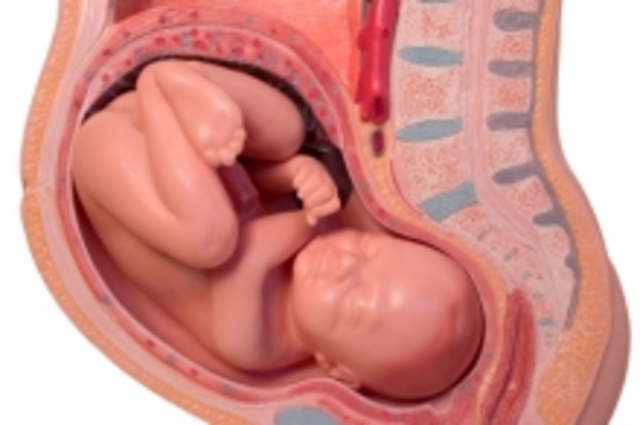

After 8 weeks the embryo becomes known as a fetus.

The yolk sac goes away and the placenta is used, which is the fetus’s life support.

The fetus will turn upside in womb which is the way it will come out.